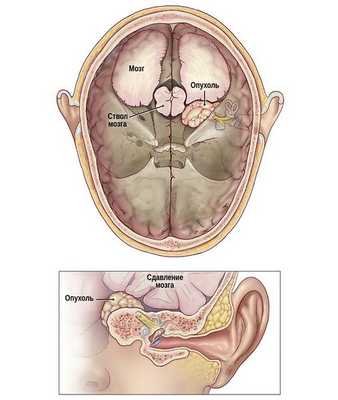

Рис. Схематичное изображение роста невриномы слухового нерва из внутреннего слухового прохода в заднюю черепную ямку со сдавление ствола головного мозга.

Вырастая, опухоль вызывает сдавление и/или растяжение улиткового нерва, которое сопровождается появлением нейросенсорной тугоухости. Иногда опухоль может сдавливать сосуды, питающие улитковый нерв (внутренняя слуховая артерия). Результатом этого, опять же, будет нейросенсорная тугоухость. По мере разрастания в области мостомозжечкового угла опухоль начинает сдавливать другие черепные нервы, а в некоторых случаях может даже приводить к угрожающему жизни сдавлению ствола мозга.

Появление тех или иных симптомов зависит от размеров опухоли и стадия её развития. Дальнейший рост невриномы ведёт к компрессии (сдавлению) 4-го желудочка и ствола головного мозга, появляются симптомы, связанные с увеличением внутричерепного давления. Например, пациент с большой опухолью может жаловаться на слабость в конечностях, асимметрию лица, тошноту, рвоту головокружение, глухоту на одно ухо.